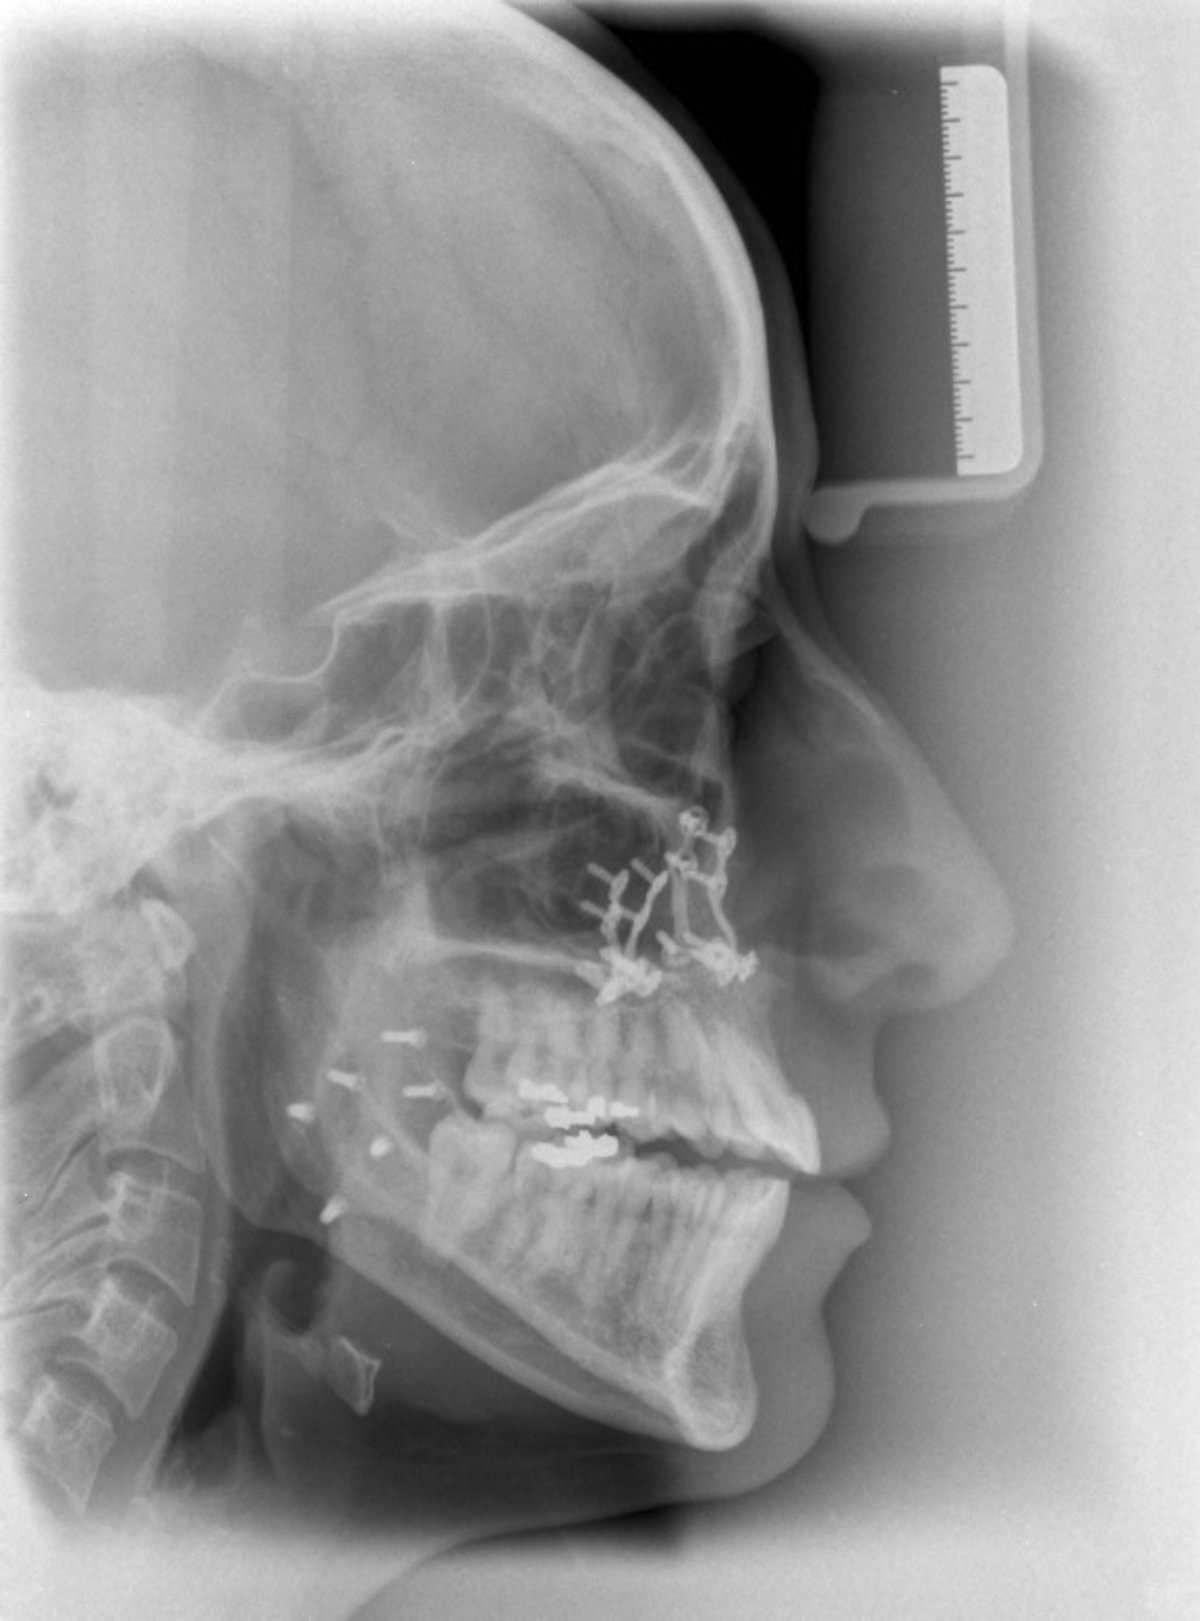

Perfil De Un Craneo En Una Radiografía